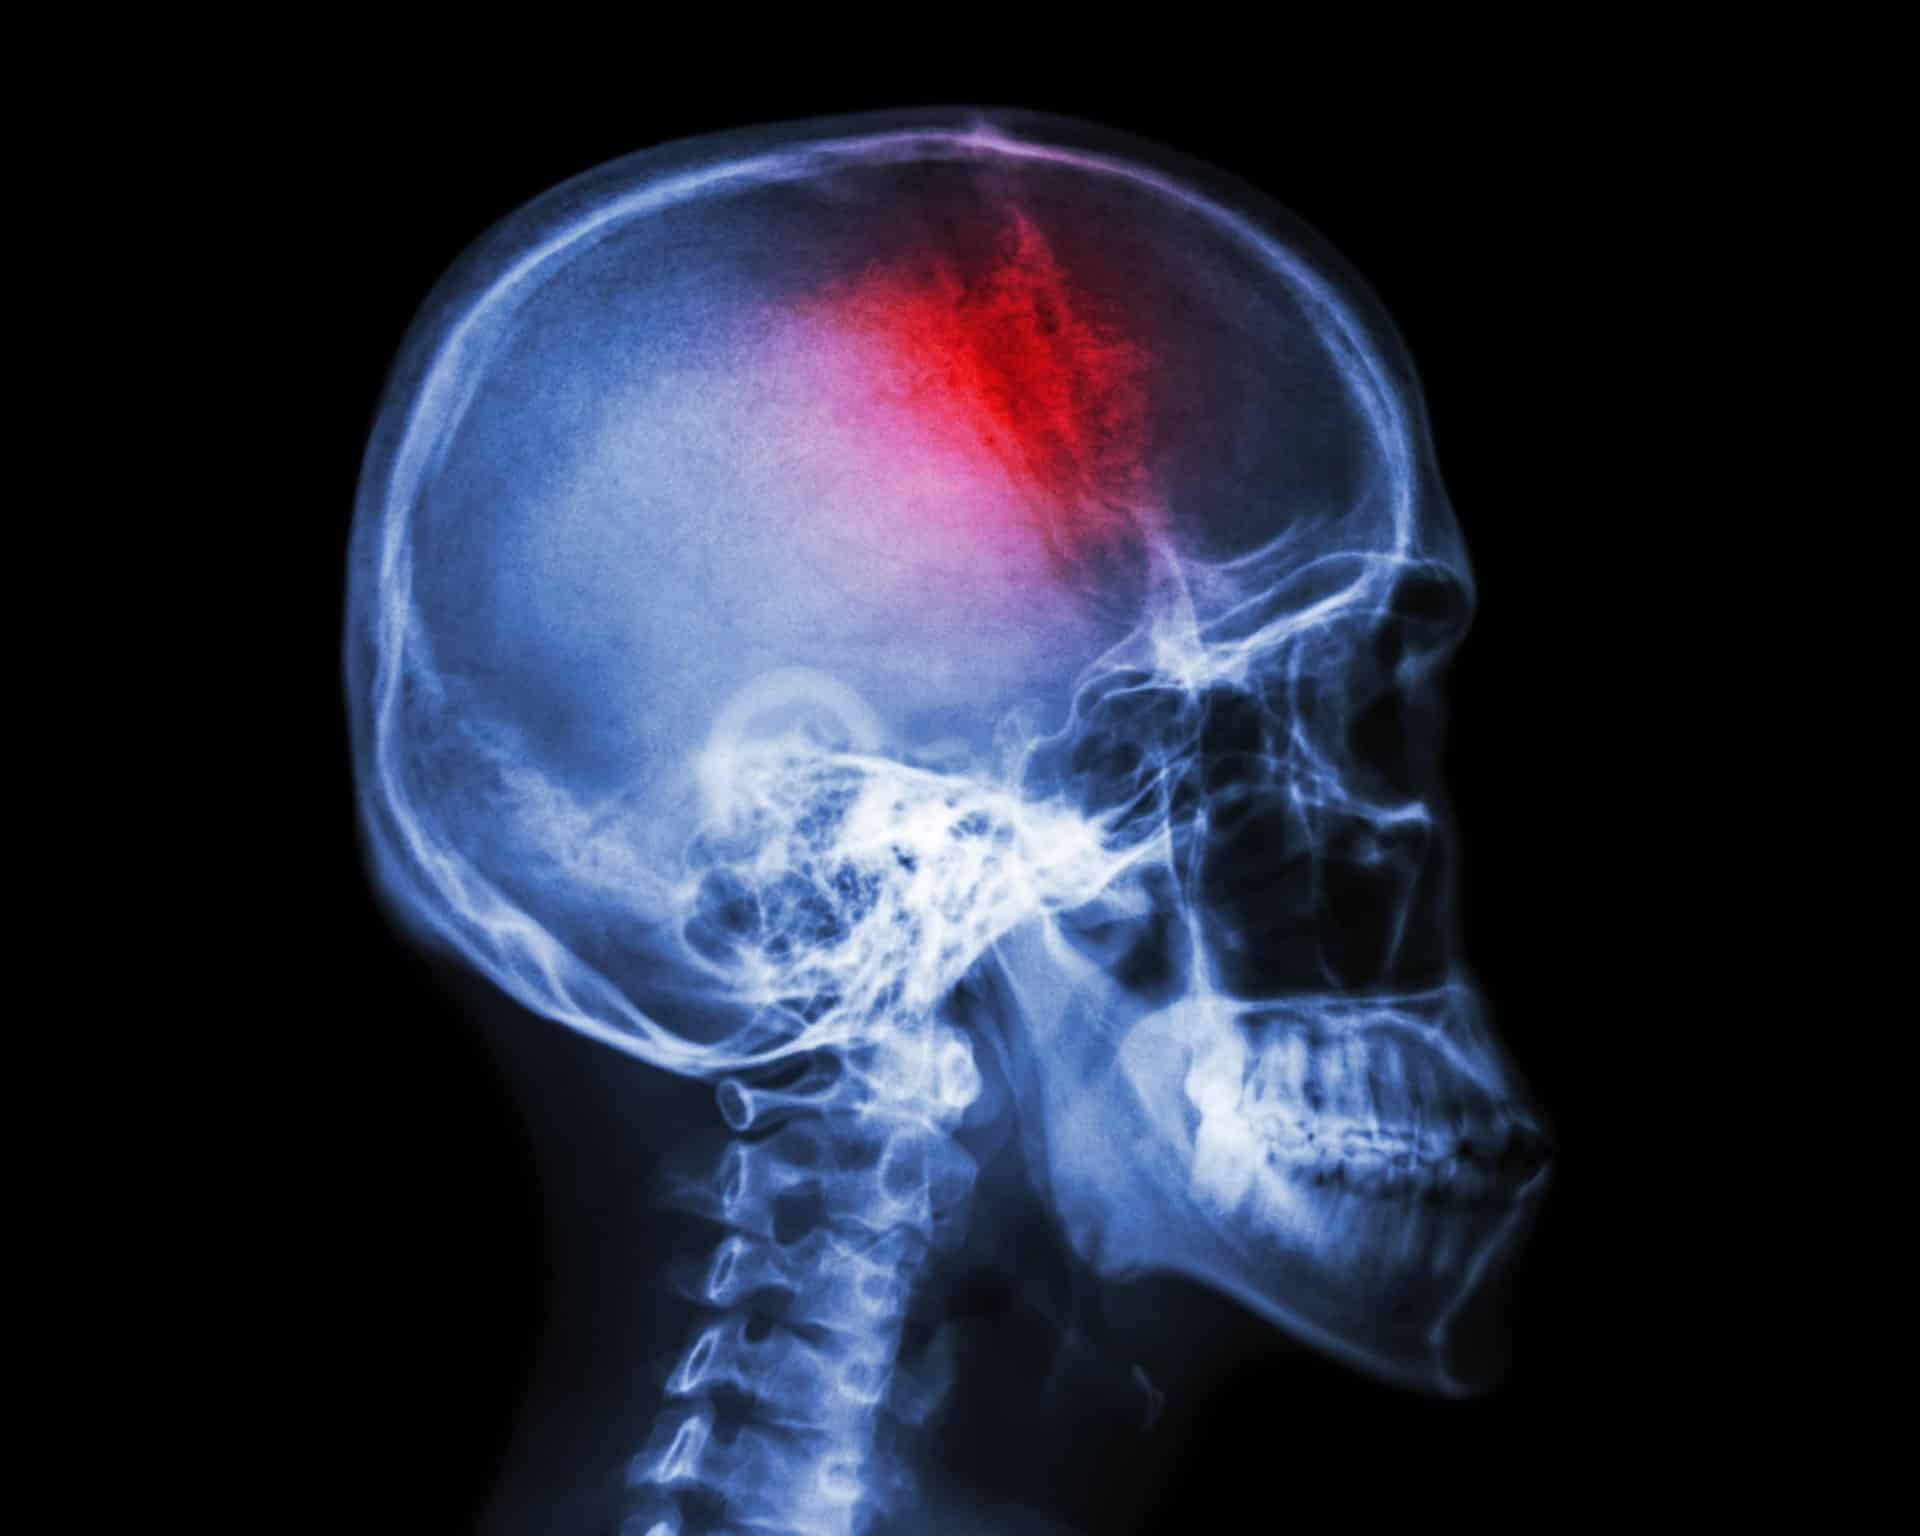

Moždani udar često se naziva i “tihim ubojicom”, trenutno je drugi vodeći uzrok smrti, treći vodeći uzrok invaliditeta u svijetu i glavni uzrok demencije. Iako većina moždani udar povezuje sa starijom dobi, zadnjih godina to je problem koji sve češće pogađa i mlade ljude. Uzrok tomu su sjedilački način života, upotreba štetnih supstanci, izloženost velikoj količini stresa, nedovoljna educiranost o simptomima te izostanak preventivnih pregleda.

Iako moždani udar najčešće nastaje naglo i neočekivano, ranim prepoznavanjem znakova i alarmiranjem hitne pomoći možete bolesniku spasiti život te znatno utjecati na povoljan ishod liječenja. Dobra informiranost i pravovremene reakcije mogu značajno doprinijeti smanjenju broja slučajeva.